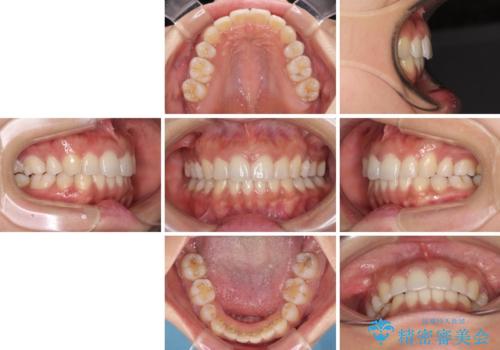

抜歯矯正の後戻り インビザラインによる再矯正治療

- 以前矯正治療をされていましたが、後戻りが起きたことを気にして来院された患者様です。

全顎的に認められた叢生を改善するため、インビザラインにて治療を行うこととしました。

前歯の叢生の改善を目的として、IPR(歯と歯の間を削る)と歯列全体の後方移動によって歯並びを整えることとしました。

毎日22時間の装着時間を守ってくださいましたが、ハイペースにマウスピースを交換することなく、慎重に治療を進めてくださったので、治療期間はやや長くなりました。

臼歯部も含め、叢生が綺麗に改善され、患者様には大変満足していただきました。